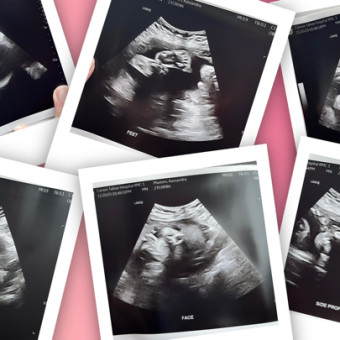

Kassandra's Baby Registry

Kassandra Masters

Reno, NV

January 25, 2026

My beautiful baby girl Maezy Rayne is expected to make her appearance January 25, 2026!